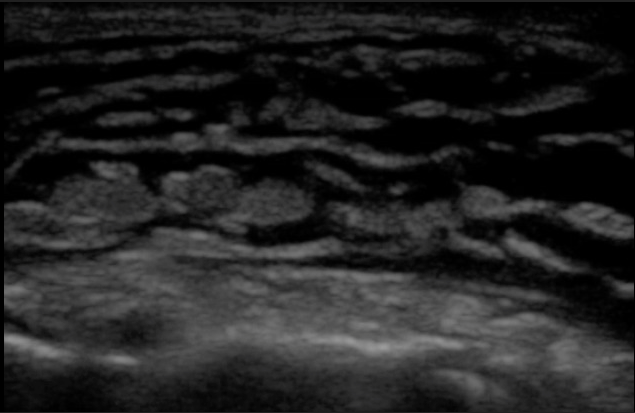

This US fidning on skin US

What is cobblestoning?

Common finding on US with edema or consolidation.

What is B lines?